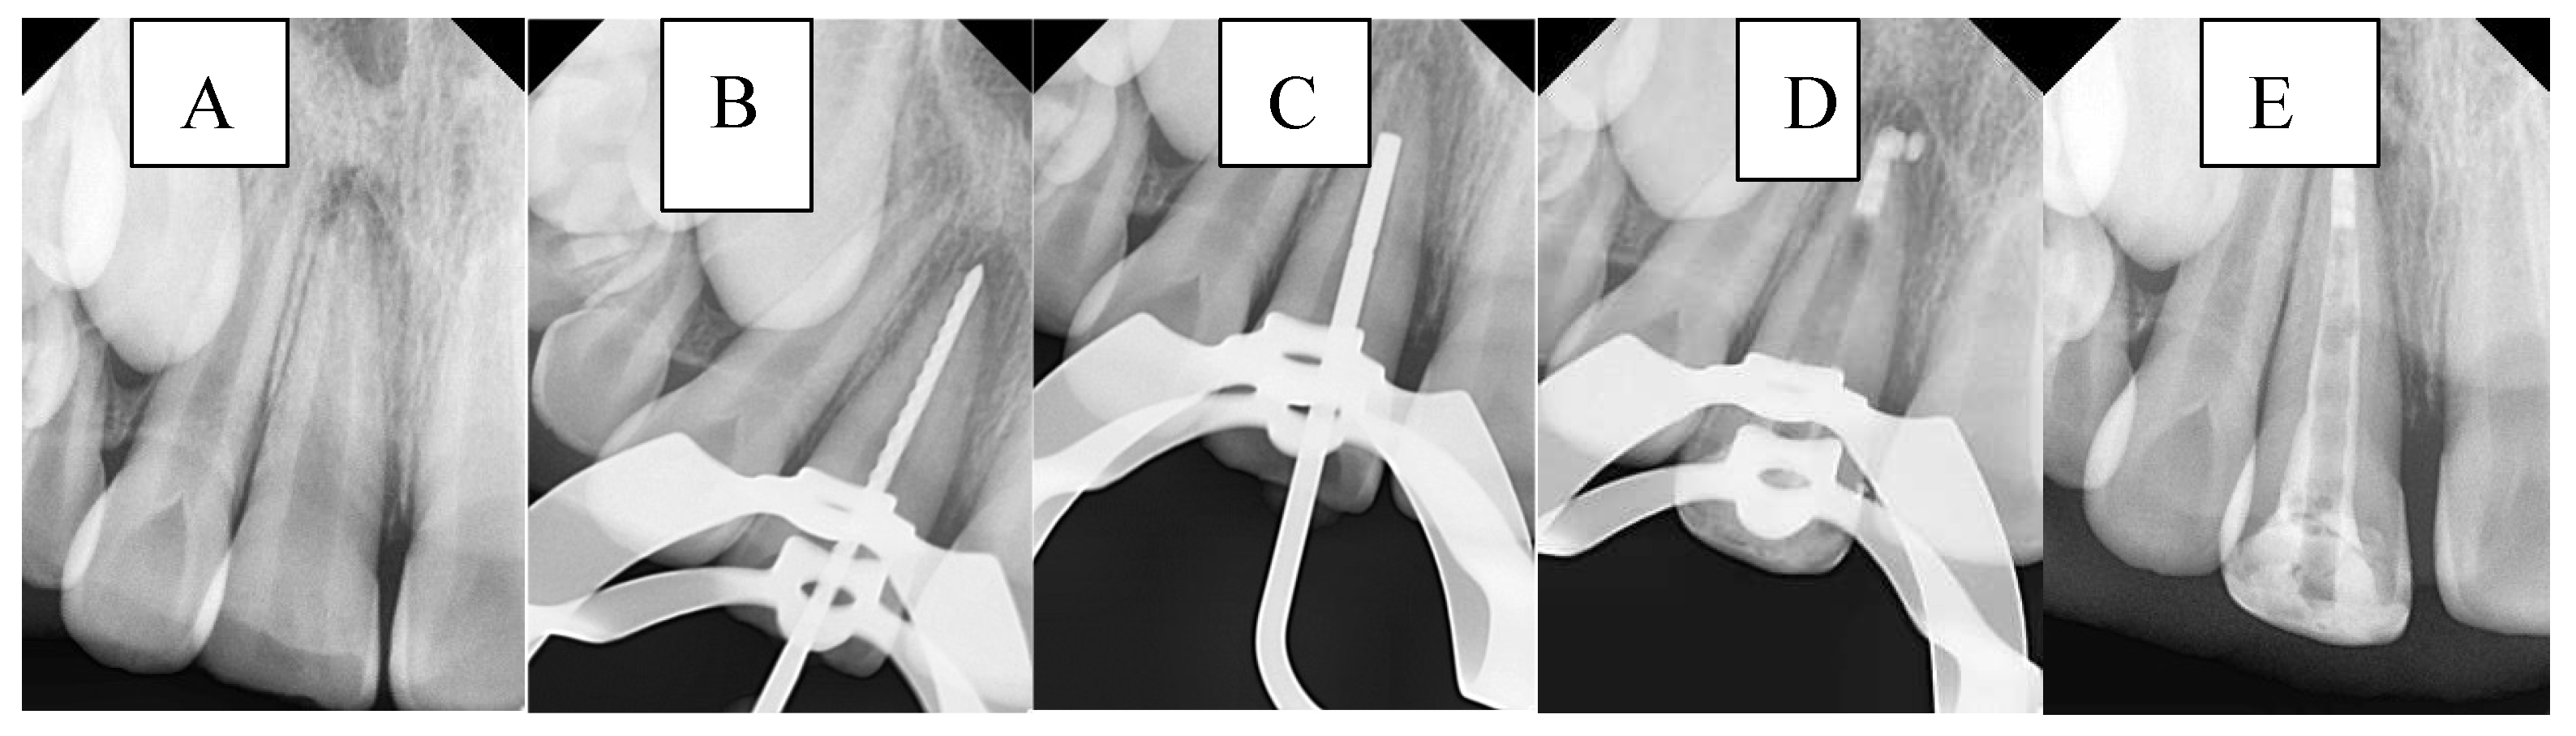

A radiograph was first taken with the hand plugger to ensure that it reached 4 mm short of the radiographic apex, as specified by the WL. The immature canal was gently filled with BC. Then, 3 to 5 small pellets (1 mm diameter) of BP were inserted into the canal orifice using a modified cannula [35] and gently plugged with hand pluggers. Finally, an apical radiograph was taken to confirm that the canal was properly filled with a 4 mm BioCeramic apical plug without gaps and voids. Any BE was recorded at this stage in the DPF. The incisors were then temporized with a cotton pellet and glass ionomer filling. The following day, after isolation and removal of the temporary filling and cotton pellet, the remaining canal space was obturated with gutta-percha and BS using the cold lateral condensation technique. A periapical radiograph confirmed that the canal was obturated without voids or gaps. Figure 4 illustrates the steps of the procedure in the BPSM group.

Figure 4. Sequential steps of the procedure in the BPSM group: A- Preoperative periapical radiograph, B- Working length radiograph, C- Plugger fit, D- Apical plug formation, E- Postoperative radiograph.